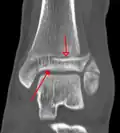

A triplane fracture of the ankle as seen on CT A triplane fracture of the ankle as seen on CT

CT

CT scans may be indicated when there is concern for a highly comminuted fracture or a fracture involving the joint surface.[10] This imaging may be used for surgical planning.